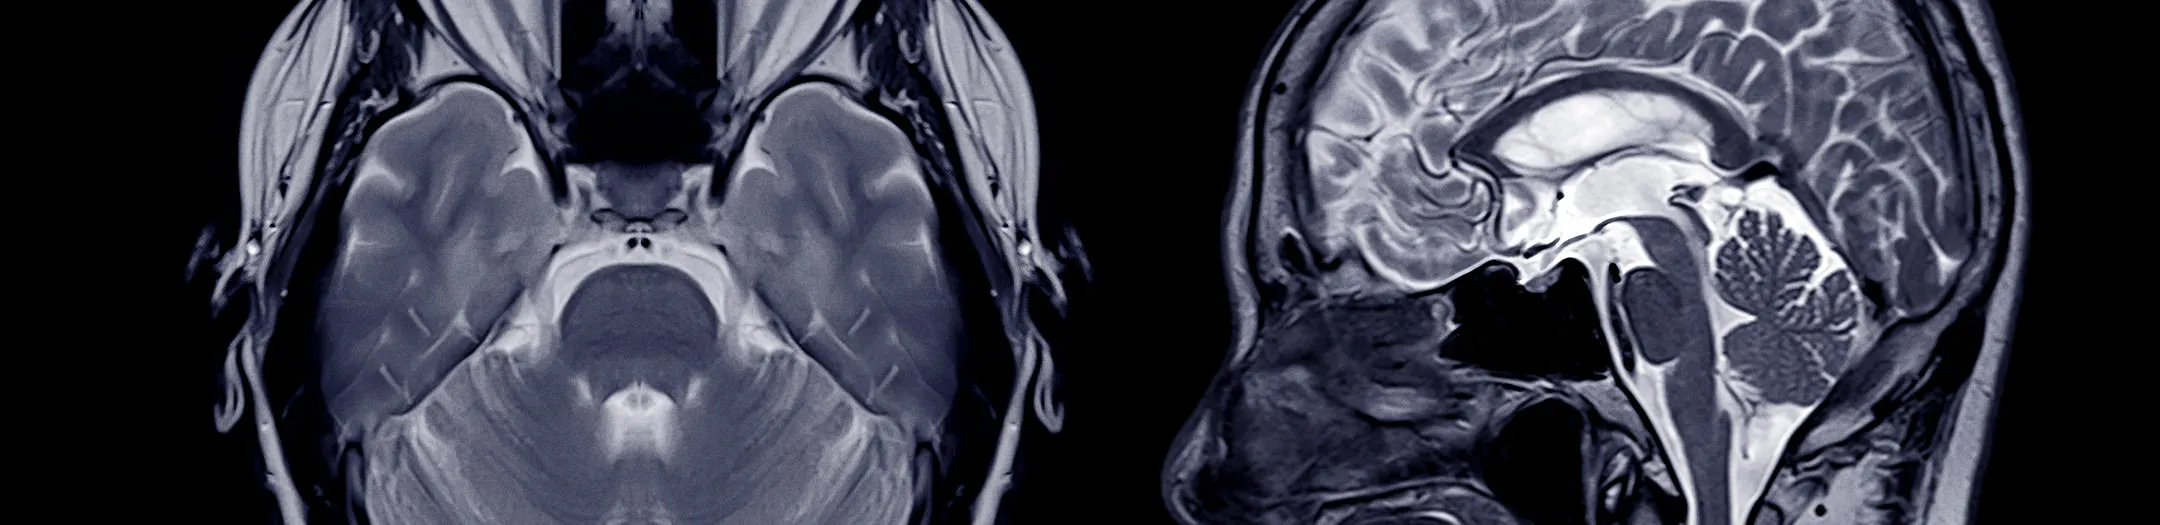

For radiology clinics: New revenue streams with minimal administrative overhead